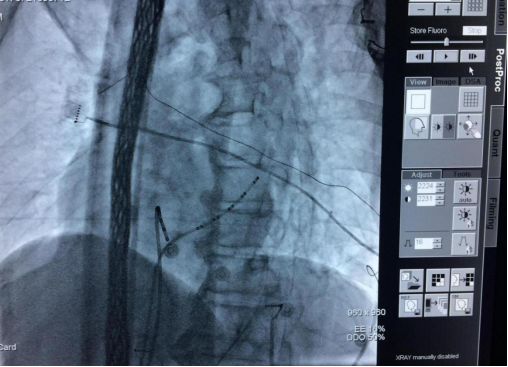

心内电生理检查

心内电生理检查是临床确诊复杂心律失常和指导其治疗的创伤性手段。其基本原理是通过多导生理仪从放置在心腔不同部位的电极导管记录心内电信号,分析心律失常的原理、类型及评价药物治疗的效果,以及分析心律失常的起源部位、定位,为导管消融及ICD治疗提供依据。操作过程是局麻下穿刺股静脉及锁骨下静脉,将2~4极电极导管送至冠状窦、高位右心房、希氏束附近及右心室,由多导仪可分别显示并记录心房(A)、希氏束(His)及心室(V)波形。希氏束电图由A、H及V3种波形组成,A代表心房兴奋活动,V代表心室兴奋活动,H由希氏束兴奋产生,A-H、H-V的距离均有正常范围,其间距过长则提示房室之间的传导阻滞。由体外的刺激器对心房和心室进行电刺激,可测定心脏不同部位组织的心电生理并可诱发不同类型的心律失常,根据A、H、V 三者的关系可对房室阻滞进行定位诊断和判断心律失常的发生机理。